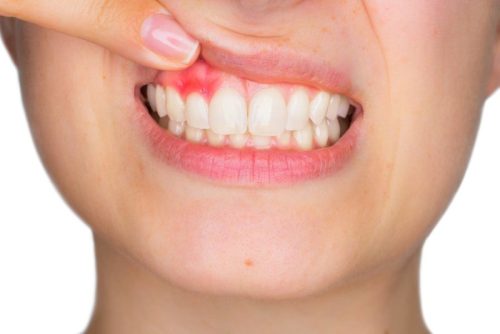

به طور کلی آبسه لثه یا دندان یک بیماری عفونی همراه با درد می باشد. که در داخل لثه یا دندان بروز پیدا می کند و شکل تورم آن قرمز رنگ است. بعضی از افراد بر این عقیده اند که آبسه صرفاً بر اثر باقی ماندن مواد غذایی بین دندان ها و تولید باکتری به وجود می آید. بله این مورد درست می باشد، اما تنها دلیل آبسه شدید دندان نیست. چرا که عوامل مختلفی نظیر پوسیدگی، شکستگی و آسیب به لثه موجب آبسه دندان و لثه می شود. پس باید بدانید که برای آبسه دندان چی خوبه و چگونه می توان درمان آبسه دندان را به روش صحیح و اصولی انجام داد تا از آسیب به سایر بخش های دهان و دندان جلوگیری به عمل آورید.

همان گونه که نام این نوع آبسه پیداست، صرفاً در ناحیه لثه بروز پیدا می کند و ربطی به دندان ندارد. با این توصیف می توان گفت هیچگونه آسیبی به دندان ها نمی رساند. اما این بدان معنی نیست که نباید درمان آبسه لثه در خانه یا مطب های دندانپزشکی را جدی نگیرید. زیرا اگر آبسه لثه پیشروی کند، ممکن است که لثه را در بر بگیرد و بدین ترتیب کنترل و درمان آن با مشکل جدی مواجه گردد. پس درمان آبسه لثه نیز مانند درمان آبسه دندان از اهمیت بالایی برخوردار است و همواره مورد توجه دندانپزشکان و متخصصان بیماری های دهان و دندان قرار دارد.

- تغییر رنگ و التهاب ورم لثه